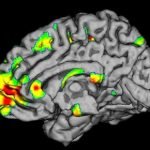

בריאות המוח הוא המרכיב השני בחשיבותו בשמירה על אורח חיים בריא. כך על פי מחקר שערך איגוד הגמלאים האמריקאי בשנת 2014. בתקופת ההזדקנות עלולות להופיע בעיות קוגניטיביות הנעות מירידה בכושר הריכוז עד למחלות כמו דמנציה ואלצהיימר.

בגיליון מרץ 2015, שמופק ע"י המכון לטכנולוגיות מזון (IFT) בארה"ב, פרסמה עורכת המחקר מאמר בו היא מונה 8 מזונות ותוספי מזון שעשויים לסייע למוח להישאר בכושר, גם בתקופת ההזדקנות.